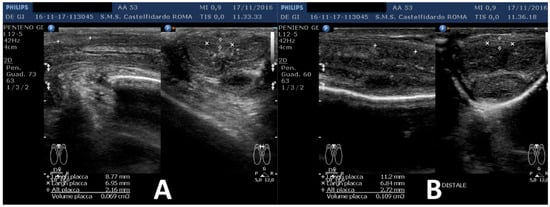

| 2 | 52 years | Dupuytren’s disease, Ledderhose disease, congenital dorsal penile curvature (5 degrees). | Middle third + distal third | (A) First plaque: 13.4 × 9.15 × 2.83 mm volume = 182 mm3. Second plaque: 14.8 × 8.43 × 3.87 mm. Total volume = 252 mm3 (B) No plaque detected | (A) 20-degree dorsal penile curvature + 20-degree left penile curvature (B) 5-degree dorsal penile curvature. Previous condition = congenital dorsal penile curvature (5 degrees) | VAS score = 0 | 26 > 27 | 51 months | Orally: propolis 600 mg + bilberry 160 mg + silymarin 400 mg + ginkgo biloba 250 mg + L-carnitine 1000 mg + coenzyme Q10 100 mg + Boswellia 200 mg + vitamin E 30 mg/daily for 51 months + topically: diclofenac gel 4%/2× daily for 51 months + periplaque penile injections: pentoxifylline 100 mg (30 G needle) every 2 weeks for 6 months, and then 1 penile injection every month for 12 months, and 1 penile injection every 2 months for 24 months (42 total injections) |